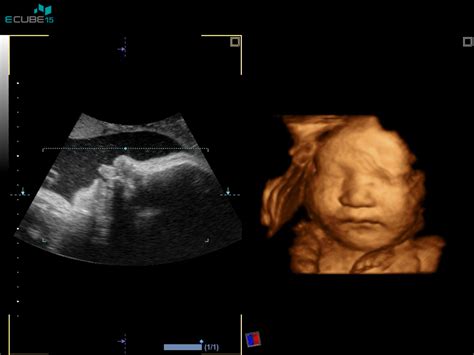

Nuhalna svetlina je majhna količina tekočine, ki se naravno nabira v podkožju v predelu zatilja ploda v prvem trimesečju nosečnosti. Meritev te tekočine je del standardnega ultrazvočnega pregleda, ki se izvaja med 11. in 14. tednom nosečnosti, natančneje med 11 tedni in 0 dnevi ter 13 tedni in 6 dnevi. Idealno obdobje za izvedbo meritve je med 11. in 13. tednom nosečnosti, saj je v tem času razvoj ploda že dovolj napredoval, da je mogoče izvesti zanesljive meritve. Prej ali kasneje opravljene meritve niso zanesljive in so lahko nejasne.

Pregled nuhalne svetline je neinvaziven, kar pomeni, da ne predstavlja nikakršnega tveganja za plod ali nosečnico. Običajno poteka preko trebuha nosečnice (transabdominalni ultrazvok), le v redkih primerih, ko plod ni v optimalnem položaju, se lahko opravi vaginalno (transvaginalni ultrazvok). Pred pregledom je priporočljivo, da ima nosečnica izpraznjen sečni mehur, kar olajša samo ultrazvočno slikanje. Sam pregled običajno traja med 10 in 15 minut, ob upoštevanju pogovora, administrativnega dela in morebitnega odvzema krvi za hormonske preiskave, pa lahko traja nekoliko dlje.

Med ultrazvočnim pregledom nuhalne svetline ginekolog_inja natančno izmeri debelino nabrane tekočine v področju zatilja ploda. Poleg tega se v tem zgodnjem obdobju nosečnosti opravi tudi pregled zgodnje morfologije ploda. To pomeni, da se natančno pregledajo ključni organi in strukture ploda, kot so srce, ledvice, možgani, okončine, želodček, mehur, hrbtenica in trebušna stena. Ocenjuje se tudi prisotnost nosne kosti v obraznem profilu ploda. Pri približno 60 % plodov z Downovim sindromom je nosna kost odsotna ali slabo razvita, medtem ko je pri 3 % normalnih plodov prav tako lahko odsotna ali slabo vidna. Jasno vidna nosna kost dodatno zniža tveganje za Downov sindrom. Pregleda se tudi srčna frekvenca ploda, njegova velikost od vrha glavice do trtice ter premer glavice. Ocenita se lega posteljice in količina plodovnice. V določenih primerih je mogoče z manjšo stopnjo gotovosti (okoli 60 %) napovedati tudi spol otroka.